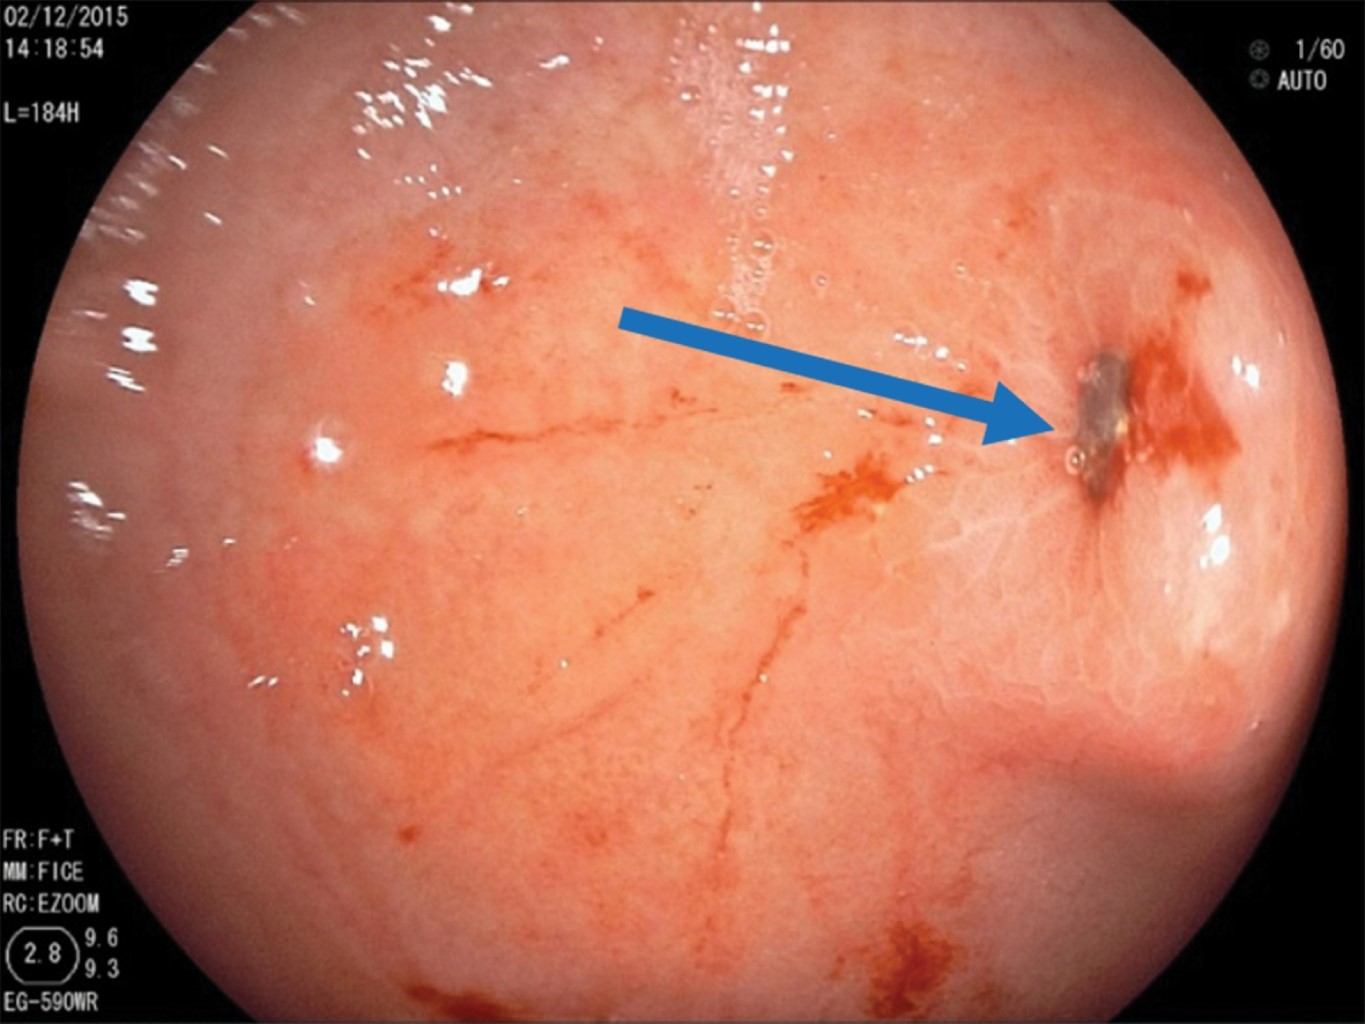

Se realiza endoscopía alta con equipo rígido en el que se aprecian tres imanes en la faringe que se extraen con pinza de caimán. Posteriormente, se efectúa panendoscopía, donde se observa esófago sin alteraciones. En estómago, a nivel del antro, se observaron ocho imanes que se extraen con red atrapa pólipos (Figura 3). Se identifica una úlcera de 4 mm con bordes congestivos y edematosos, en su interior se encuentra un imán incrustado (Figura 4). En el duodeno no se identifican lesiones.

Figura 4